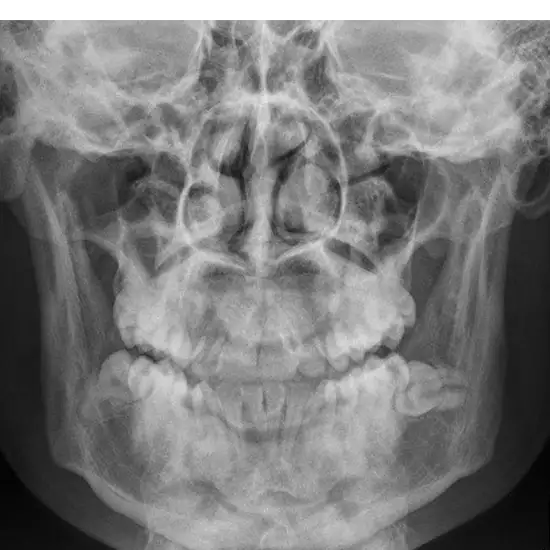

An X-ray of the mandible (right) (AP view) is typically obtained after a traumatic event to confirm a fracture or dislocation. If you've been in an accident and have these symptoms, see a doctor immediately.

Mandible (AP View) X-rays are often used to determine a dislocation or fracture of the mandible.